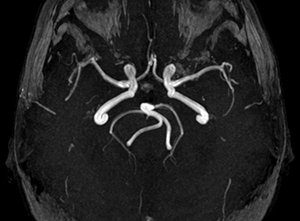

Диагностика аномалий

В распознавании артериальной патологии основания мозга недостаточно визуального (неврологического и офтальмологического) осмотра.

Посему прибегают к инструментальному исследованию сосудов методами:

- ультразвуковой допплерографии;

- МРТ (магнитно-резонансной томографии);

- рентгеноконтрастной ангиографии;

- транскраниальной допплерографии;

- магнитнорезонансной ангиографии;

- селективной ангиографии.